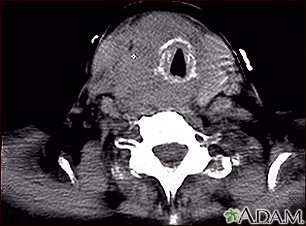

Thyroid cancer - CT scanBackThyroid cancer - CT scanThis CT scan shows a thyroid cancer tumor in the throat, encircling, narrowing, and displacing the windpipe (trachea). E-mail FormEmail ResultsName:Email address:Recipients Name:Recipients address:Message: